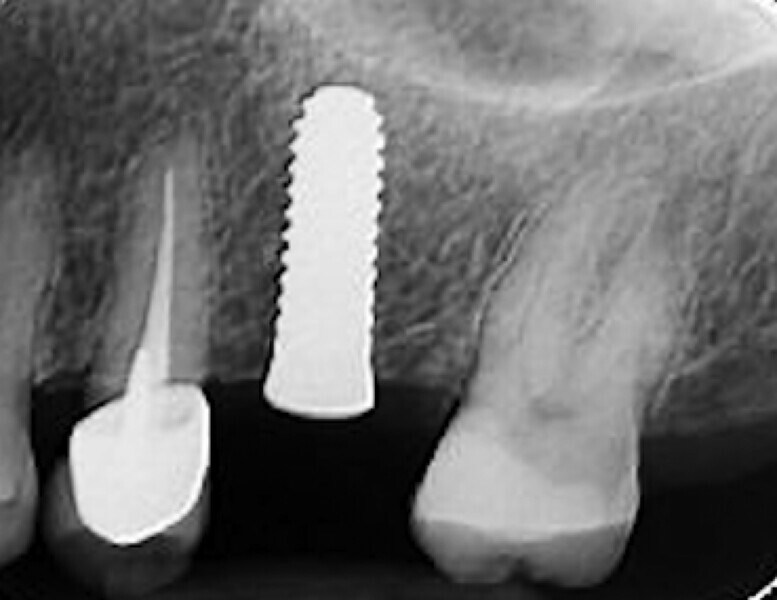

Fig. 1 : Radiographie avant l’extraction (première phase).

Fig. 2 : Radiographie avant l’extraction (première phase).

La première phase du traitement implantaire a consisté à extraire la dent et à préserver l’alvéole au moyen d’une allogreffe et d’une membrane de collagène. Six mois après, l’os régénéré a permis de procéder à la seconde phase du traitement comportant la pose d’un implant deux pièces en céramique (Figs. 1–11).